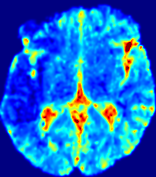

LesionRefer to captionRefer to captionRefer to captionRefer to captionRefer to captionRefer to caption𝐕rgbsubscript𝐕𝑟𝑔𝑏{\bf{V}}_{rgb}Refer to captionRefer to captionRefer to captionRefer to captionRefer to captionRefer to caption𝐕2subscriptnorm𝐕2{\|\bf{V}}\|_{2}Refer to captionRefer to captionRefer to captionRefer to captionRefer to captionRefer to captionRefer to caption3.53.53.52.82.82.82.12.12.11.41.41.40.70.70.70.00.00.0(mm/s)𝑚𝑚𝑠(mm/s)D𝐷DRefer to captionRefer to captionRefer to captionRefer to captionRefer to captionRefer to captionRefer to caption0.0200.0200.0200.0160.0160.0160.0120.0120.0120.0080.0080.0080.0040.0040.0040.0000.0000.000(mm2/s)𝑚superscript𝑚2𝑠(mm^{2}/s)Slice #1Slice #2Slice #3Slice #4Slice #5Slice #6

Figure 4: PIANO feature maps for another patient in the ISLES 2017 training set, where the lesion is located in the right hemisphere. Top row: segmented stroke lesion region (white) on different slices. The corresponding slices for the PIANO feature maps are shown in the following rows.

For a better insight into an estimated velocity field 𝐕𝐕{\bf{V}} and diffusion field 𝐃𝐃{\bf{D}}, we compute the following maps: (1) 𝐕rgbsubscript𝐕𝑟𝑔𝑏{\bf{V}}_{rgb}: Color-coded orientation map of 𝐕=(Vx,Vy,Vz)T𝐕superscriptsuperscript𝑉𝑥superscript𝑉𝑦superscript𝑉𝑧𝑇{\bf{V}}=(V^{x},V^{y},V^{z})^{T}, obtained by normalizing 𝐕𝐕{\bf{V}} to unit length and mapping its 3 components to red, green, blue respectively; (2) 𝐕2subscriptnorm𝐕2\|{\bf{V}}\|_{2}: 222 norm of 𝐕𝐕{\bf{V}}; (3) D𝐷D: scalar field in Eq. 5.

Fig. 3 and Fig. 4 show the PIANO feature maps estimated from two ISLES 2017 patients: all are highly consistent with the lesion in both cases. Details of the blood flow trajectories are revealed in 𝐕rgbsubscript𝐕𝑟𝑔𝑏{\bf{V}}_{rgb} by the ridged patterns and the sharp changes of colors in the unaffected (right) hemisphere, while the flat patterns appearing within the lesion provide little directional information about the velocity and indicate low velocity magnitudes. Velocity magnitudes are more directly visualized via 𝐕2subscriptnorm𝐕2\|{\bf{V}}\|_{2}, from which one can easily locate the lesion where 𝐕2subscriptnorm𝐕2\|{\bf{V}}\|_{2} is low. D𝐷D also indicates lower diffusion values in the lesion, though with less contrast potentially due to the fact that it captures the accumulated effect of CA diffusion at the voxel-level.